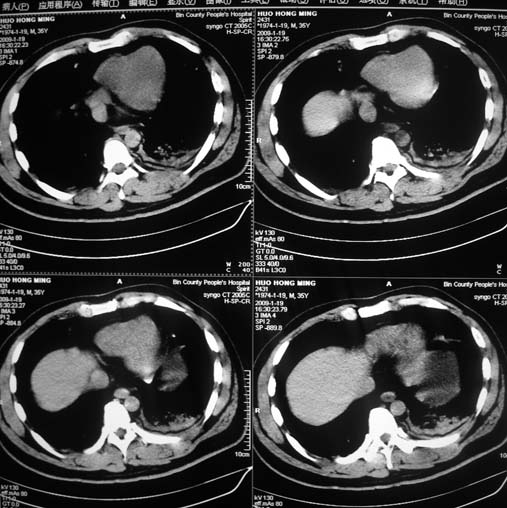

以下是引用余辉在2009-1-20 8:22:00的发言:[br]右侧肾上腺明显增大、边缘不光整,肯定有问题,结合患者病史考虑肾上腺挫伤、伴血肿形成。[br]另左肾后唇包膜下方可见局限性新月形高密度影,考虑肾包膜下出血[br]余同意楼上,建议增强排除脾破列

以下是引用随光逐影在2009-1-20 8:21:00的发言:[br]1)左侧多发肋骨及部分腰椎左侧横突骨折。2)左侧肾旁后间隙及同侧胸腔积血。3)左侧腰大肌肿胀。